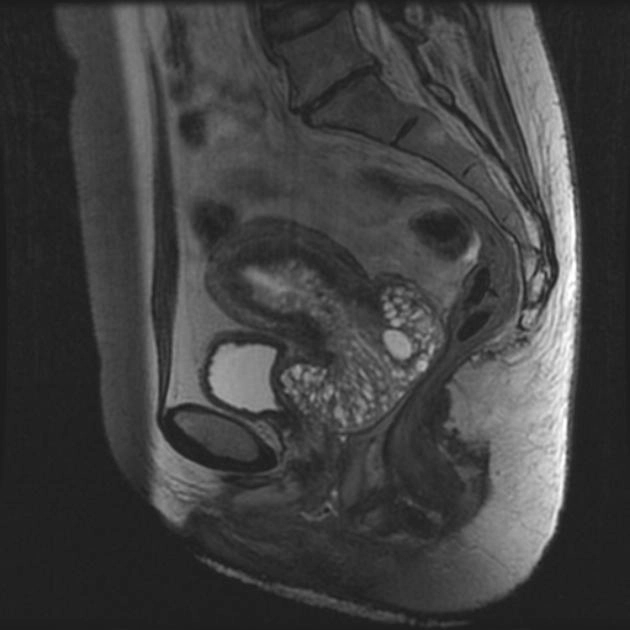

Carcinoma cổ tử cung (Cervical carcinoma)

Phân loại giai đoạn ung thư cổ tử cung (Cervical cancer staging)

Ung thư tuyến cổ tử cung ít ác tính (Adenoma malignum of the cervix)